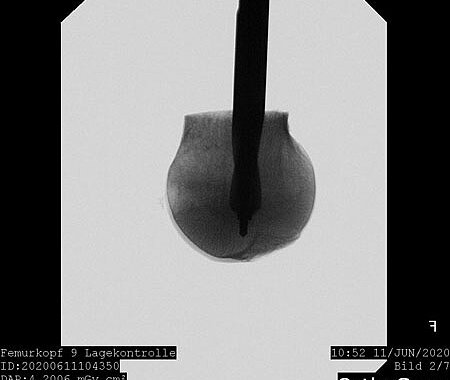

Our research currently focuses on optimizing mineral bone cements for clinical use. The necessary basic components for calcium phosphate and magnesium phosphate cements are combined in such a way that the desired properties – such as sufficient viscosity for injection and subsequent hardening with high load-bearing capacity – are optimized.